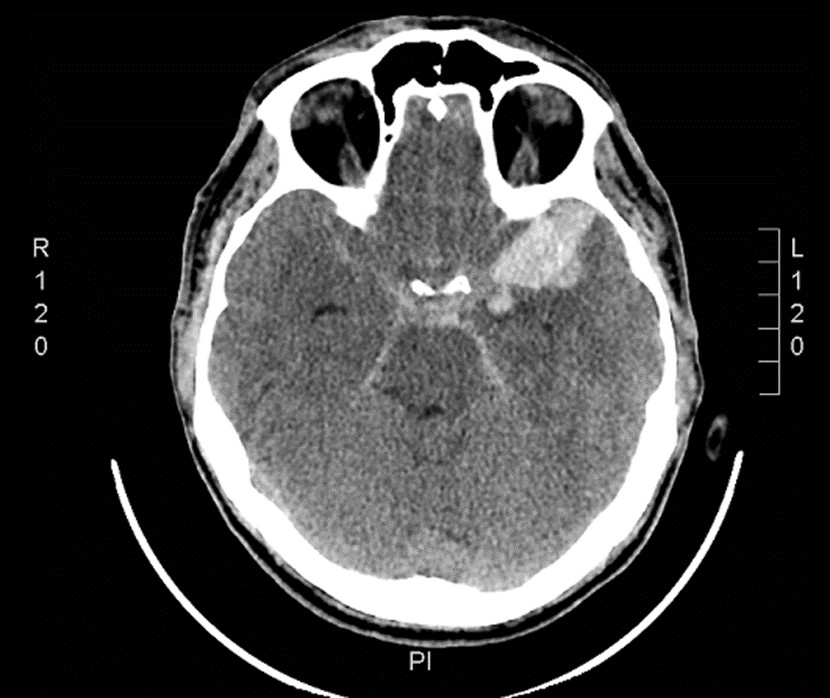

47-letni chory został przewieziony do SOR z miejsca pracy, gdzie doznał nagłego silnego bólu głowy, po którym nastąpiły nudności i wymioty. Przy przyjęciu GSC 15 pkt. Źrenice równe, prawidłowo reagujące na światło. Bez objawów ogniskowego uszkodzenia OUN. Sztywność karku na 2 palce. Wykonano badanie TK głowy, które wykazało cechy krwotoku podpajęczynówkowego (skan poniżej). Oceń stan chorego w skali WFNS i badanie TK w skali Fishera na podstawie podanych informacji:

Zaburzenia świadomości, nudności, bóle głowy oraz obraz badania TK głowy jak poniżej może sugerować: